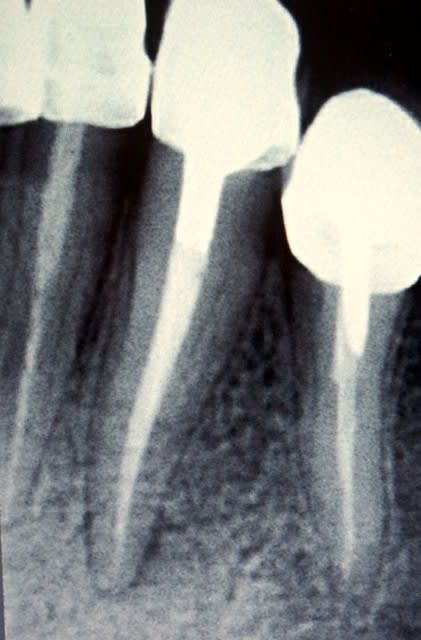

Ci-joint des radios d'une 12 qui présente d'abord un indice 1 puis qui est passé en indice 2 en l'espace de 2 mois. Je vous rassure, je n'avais pas fait le traitement initial (pas si horrible que ça), ni le compo. J'ai donc opté à l'époque pour le retraitement.

suite de la démo avec le passage d'une lésion que l'on pourrait qualifier de 4 (voire 3 si on compare avec ce que nous donne comme exemple les auteurs dans leur article) sur la radio initiale en une lésion de type 2 (en cours de cicatrisation) 3 mois après le retraitement.